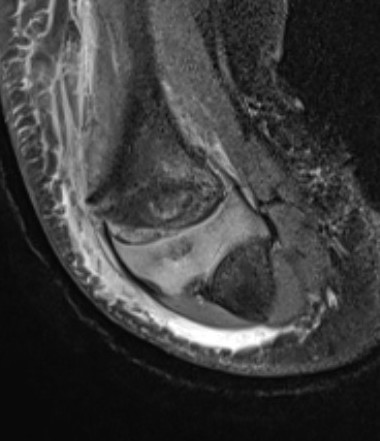

Ultrasound

MRI

Arthrogram

May need arthrogram to visualize distal humerus epiphysis